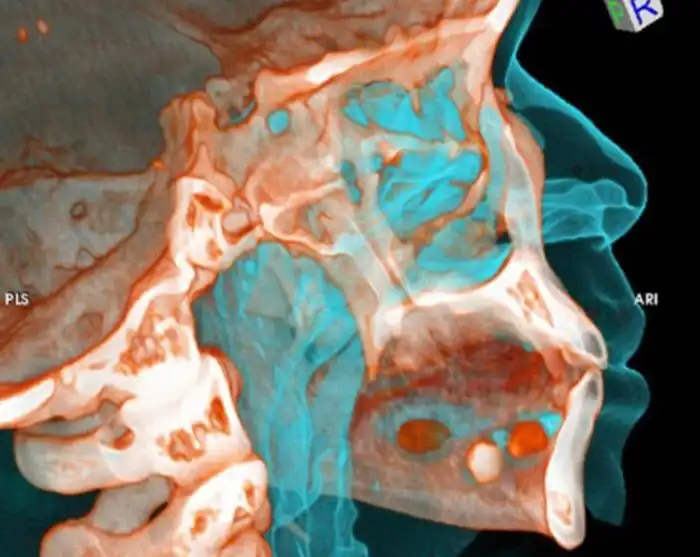

Пакетики с кокаином под языком

Попытка провезти кокаин под языком

Одна часть кокаина под языком, а вторая в желудке